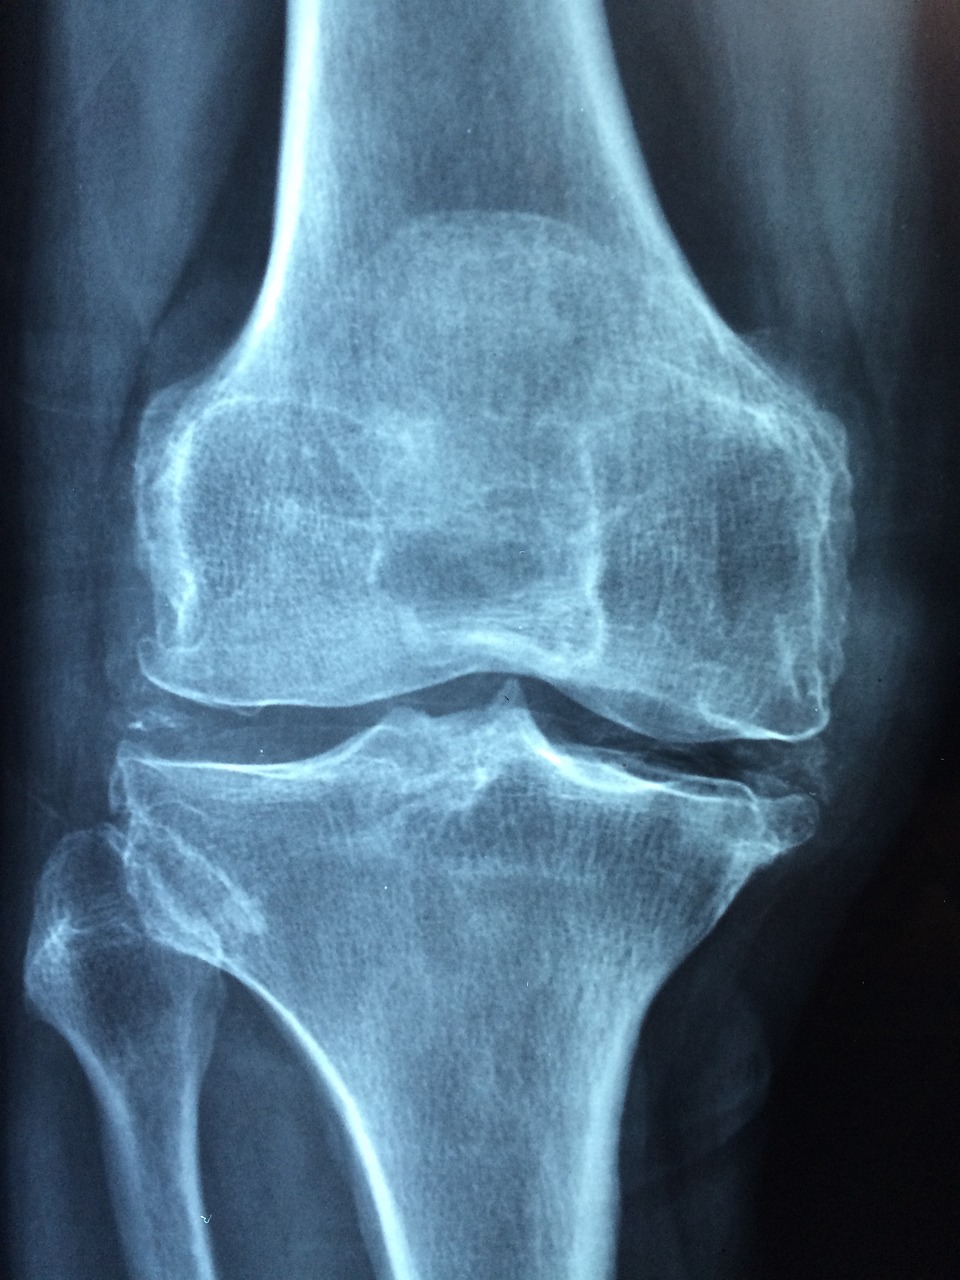

나이가 들면 자연스럽게 무릎 통증이 찾아오고, 심할 경우 인공관절 수술을 받아야 하는 상황이 생기곤 합니다.

무릎 인공관절 수술은 평균적으로 한쪽 무릎 기준 300만 원 이상의 비용이 들 수 있습니다.

- 건강보험 기준 ‘인공관절치환술(슬관절)’ 필요 질환자

※ 병원 진단서 등 '슬관절 인공관절이 필요한 상태'임을 증명할 수 있어야 합니다.

무릎 인공관절 수술은 고통을 줄이고 삶의 질을 크게 향상시키는 치료입니다.